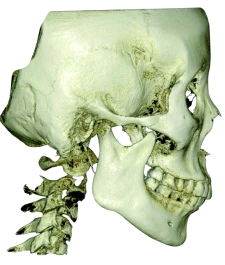

RAYSCAN 18х16 может с лёгкостью и точностью охватить обширную область анатомии. Его замечательная способность захватывать как назион, так и глабеллу, область от подбородка до лба, всё это в одном сканировании высотой 16 см действительно впечатляет.

Ортодонтия & ЧЛХ

- Оценка роста

- Анализ симметрии лица

- План ортодонтического лечения

- Анализ дыхательных путей и ВНЧС

- Моделирование ортогнатической хирургии